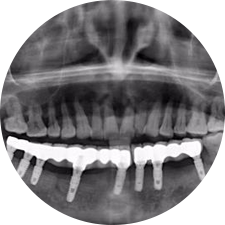

術前患者CBCT口掃1:1三維重建,模擬手術過程及預測術后治療效果,確定每顆植體植入的適合的種植位點、深度及角度,有效避免損傷頜骨重要解剖結構,提高手術準確度與安全性。

術前將患者口內的CBCT數據及咬合關系上傳到計算機中,建立1:1三維重建,模擬手術過程及預測術后治療效果,找出較佳種植位點、深度及角度,獲取實際種植體在頜骨內的具體三維位置,有效避免損傷頜骨重要解剖結構,大大降低手術風險,提升種植成功率。